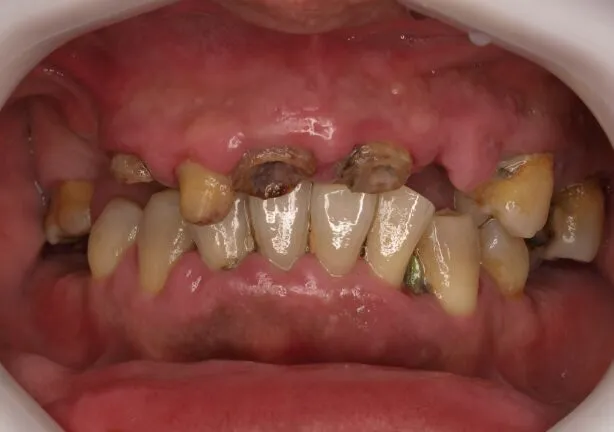

症例

case1

Before

治療内容 | 口腔内診査〜カウンセリング

仮の義歯にて咬む位置の再設定 インプラント埋入 仮歯にてインプラントを含めた咬む位置の決定 最終的な被せ物(ジルコニア)の型取り〜装着 |

治療期間 | 4年(月2回の治療を要望されたため) |

治療回数 | 約100回 |

費用(税込) | 約¥8,800,000 |

リスク | 手術、並びに治療における疼痛 今後のメンテナンスが必須となる |